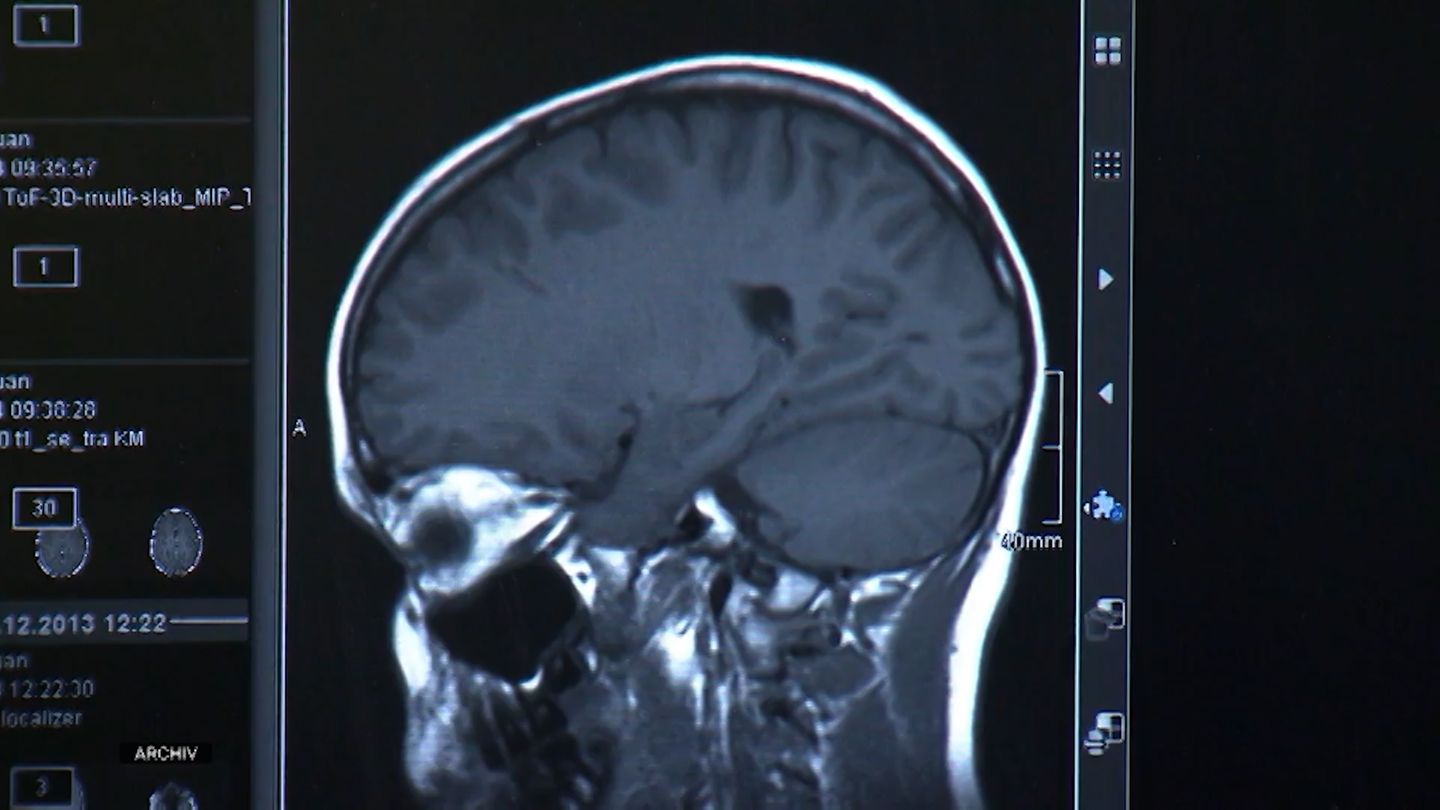

Prognose bis 2050: Zahl der Parkinson-Erkrankungen könnte drastisch steigen

Durch Feinstaubbelastung und Verwendung von Pestiziden könnte die Zahl der Parkinson-Erkrankungen bis 2050 drastisch ansteigen. Doch es gibt Wege, dem entgegenzuwirken.

Durch Feinstaubbelastung und Verwendung von Pestiziden könnte die Zahl der Parkinson-Erkrankungen bis 2050 drastisch ansteigen. Doch es gibt Wege, dem entgegenzuwirken.

Durch Feinstaubbelastung und Verwendung von Pestiziden könnte die Zahl der Parkinson-Erkrankungen bis 2050 drastisch ansteigen. Doch es gibt Wege, dem entgegenzuwirken.